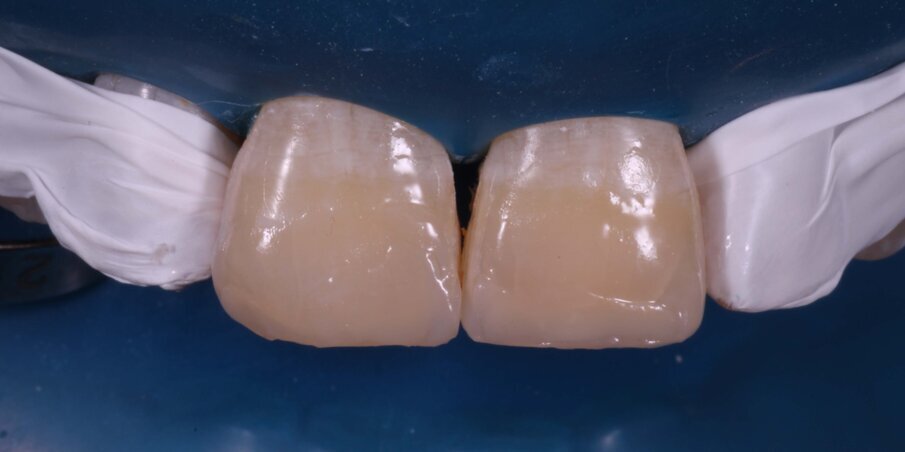

Finishing was carried out with finishing discs (Shofu Snap-on Discs) and Soflex Spirals (3M ESPE). Polishing was done with Prisma Gloss polishing paste (Dentsply) and a rubber cup (Fig 15). Thus the reverse smile was corrected by a simple restoration of fractured incisal edges. The patient reported back to us with a renewed sense of confidence after her smile-rejuvenation (Fig 16-17).

Fig 15. Post op image

Fig 16. Two-week post op

Fig 17. Final smile